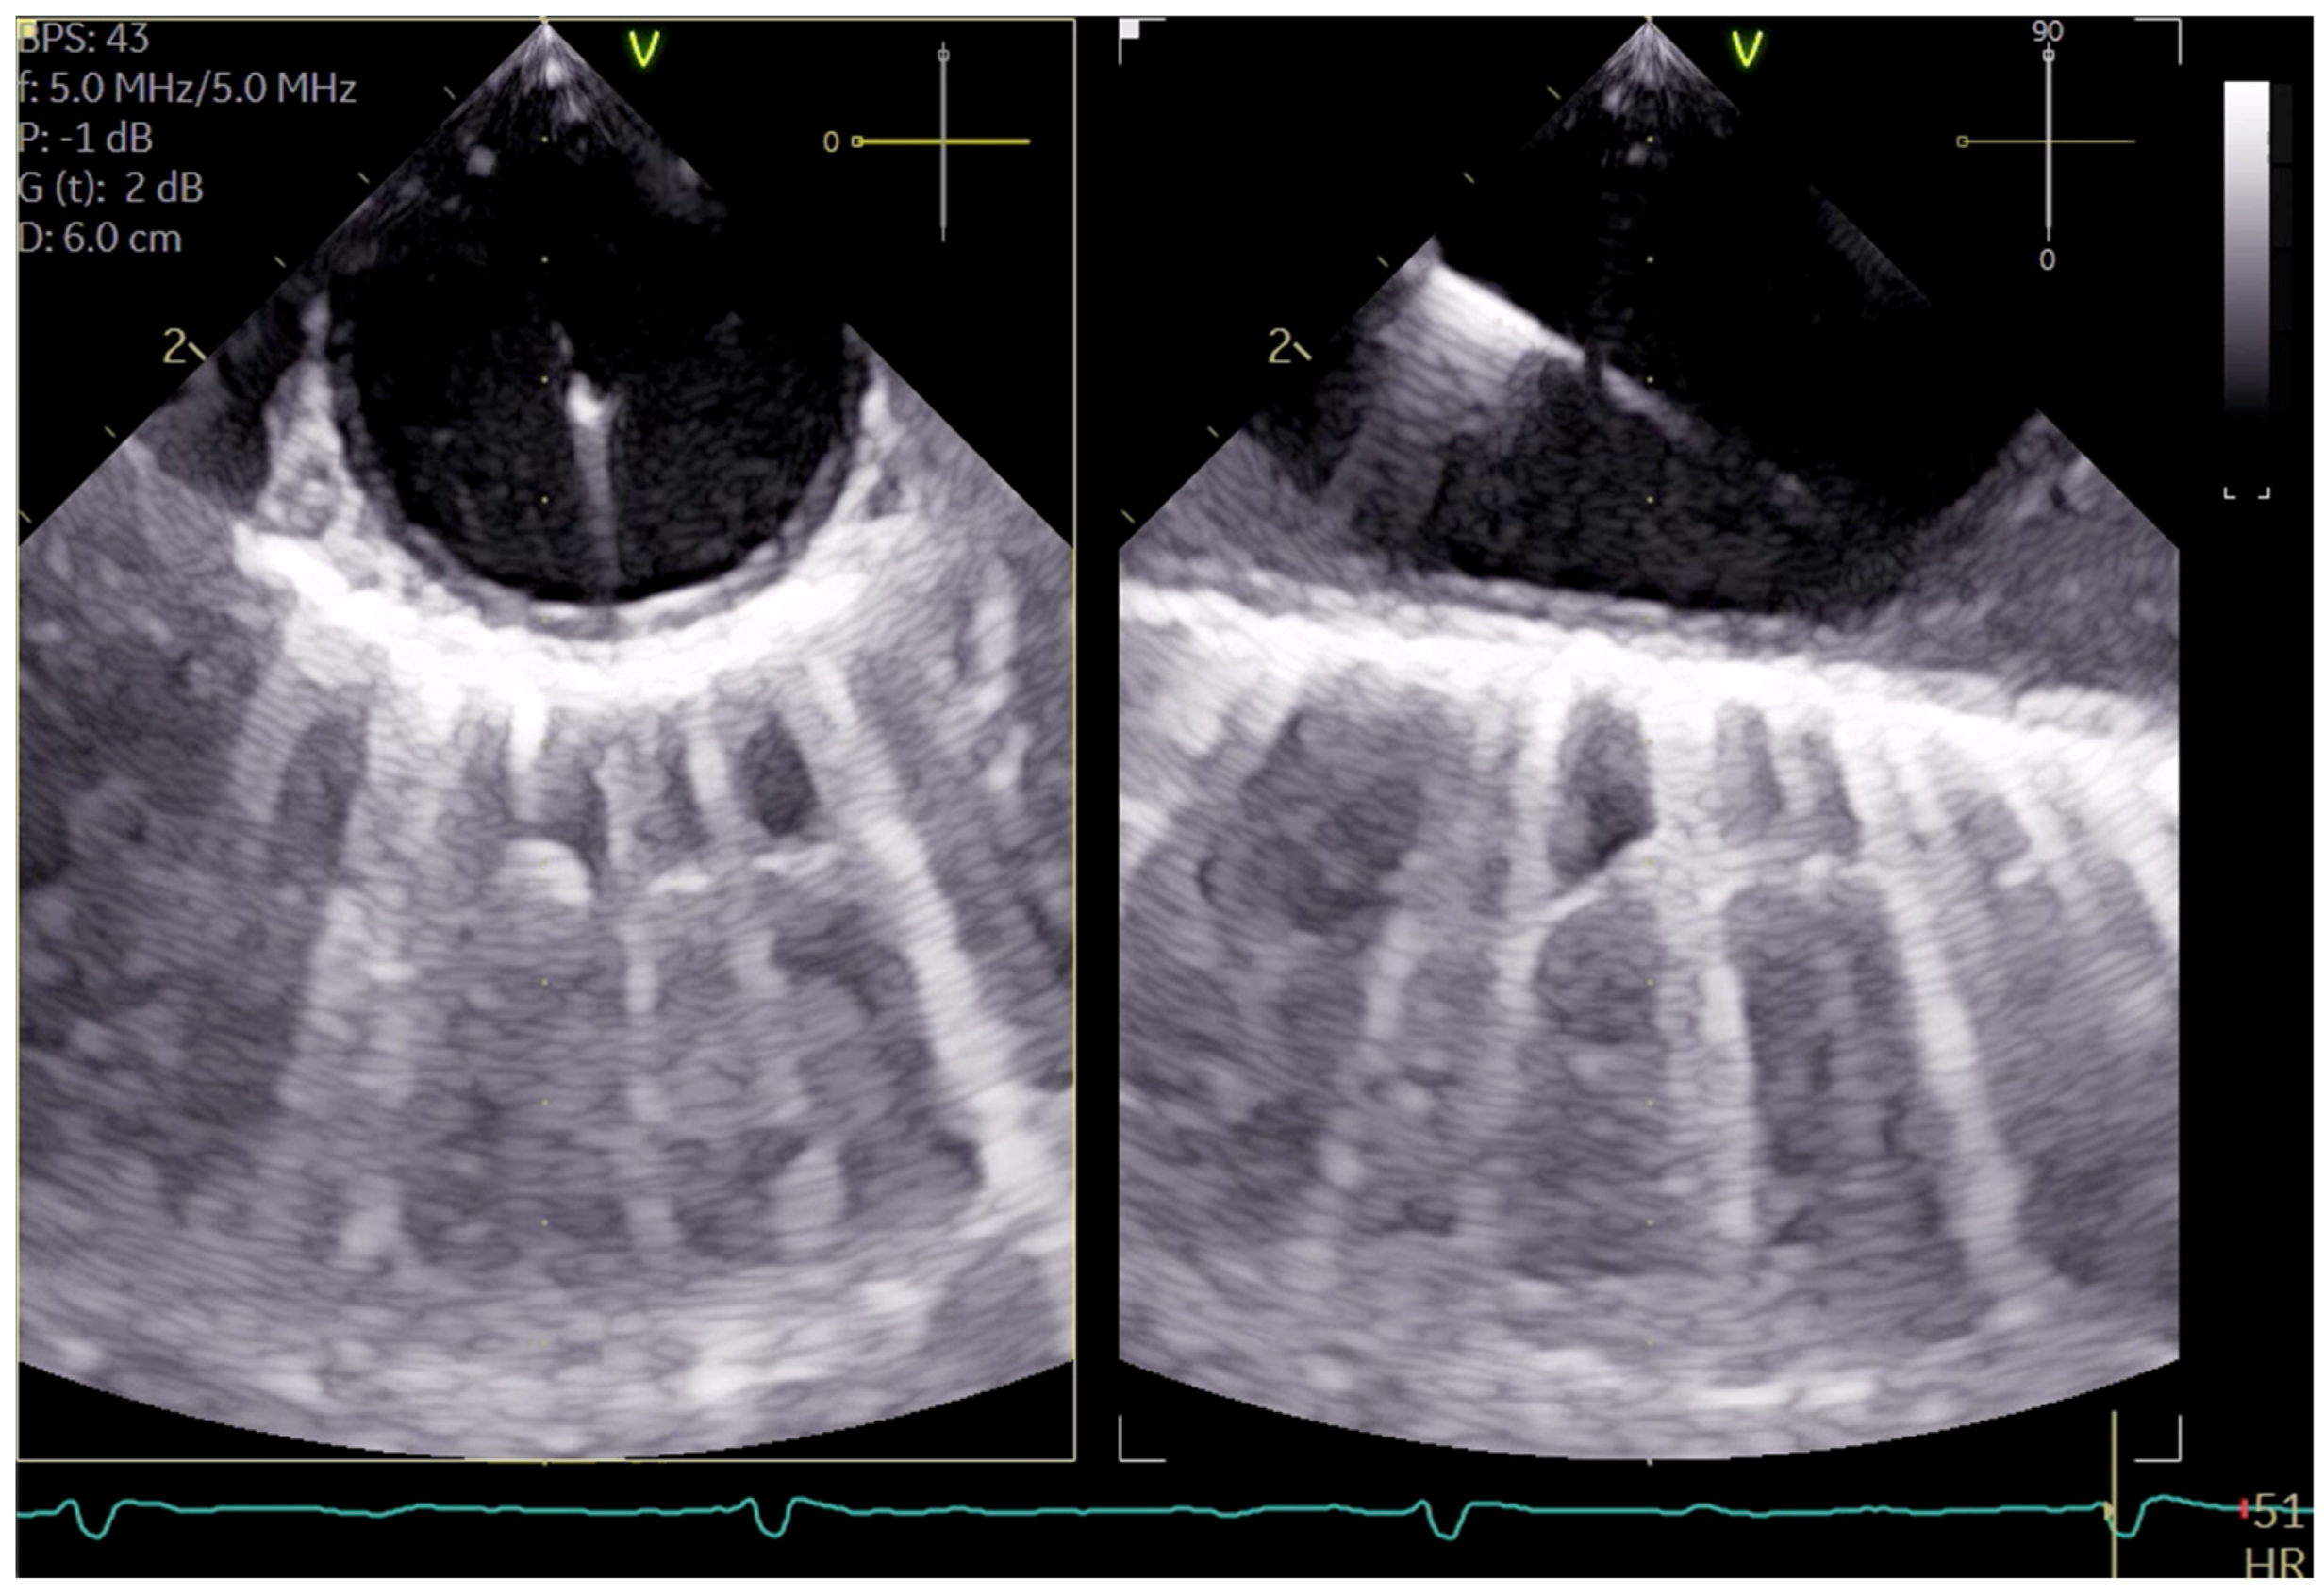

The SVC drainage cannula (Edwards Fr 16/18 OptiSite arterial cannula) is placed via the right jugular vein under ultrasound guidance simultaneously with the central venous catheter insertion. The cannula is positioned caudally to the central venous catheter and other venous lines (see Figure 3a,b). It is important to note that cannulation is performed above the superior thorax aperture to avoid potential complications resulting from intrathoracic vascular damage. We do not perform side-separated cannulation of the central venous catheter and CPB cannula at our center. This approach offers advantages in terms of time management and protection of the contralateral side for possible subsequent punctures during hospitalization. No adverse effects were observed in association with the multiple access procedure.

Figure 3.

(a) shows the catheters inserted in the internal jugular vein right from cranial to caudal as follows: central 4-lumen central venous catheter, 1-lumen 9 FR catheter, and the CPB cannula; (b) shows three guidewires in the right internal jugular vein.